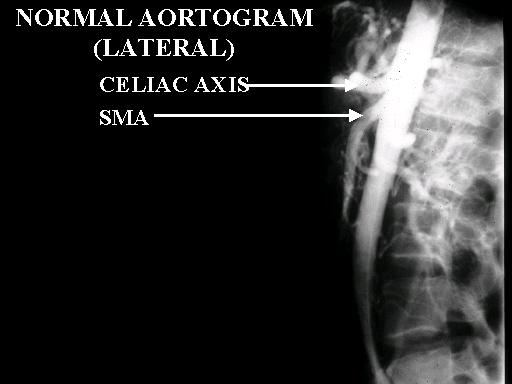

MS 119 AGRAM LAT